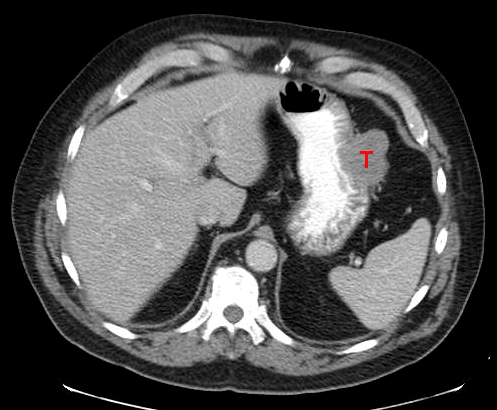

Στρωματικοι όγκοι-GIST

Στρωματικοι ογκοι

Οι στρωματικοι όγκοι ανήκουν στους μεσεγχυματικους όγκους και απαντώνται στο γαστρεντερικό σύστημα.Ειναι σπάνιοι και προέρχονται από τα πολυδύναμα βλαστικά κύτταρα .Κατα 50-60% απαντώνται στον στον στόμαχο .Θεωρούνται δυνητικά κακοήθεις όταν ξεπερνούν τα 5 εκατοστά.

Όταν είναι κακοήθεις δίνουν μεταστάσεις αιματογενως (ήπαρ ,περιτοναιο) η από αποπτωση κυττάρων .

Τα συμτωματα είναι : προεξάρχον η αιμορραγία και άτυπα όπως ναυτία ,εμετοί ,δυσφορία ,αίσθημα κορεσμού .

Η κυρίως διαγνωστική εξέταση είναι η οισοφαγογαστροσκοπηση, αξονική τομογραφία η και ενδοσκοπικό υπερηχογράφημα.

Η θεραπεία είναι χειρουργική συν την ιματινιμπη (αναστλεας BRC-ABL ογκοπρωτεινης ) η οποία χρησιμοποιειτα κυρίως στη χρόνια μυελογενή λευχαιμία,και η οποία έφερε επανάσταση στις μεταστάσεις από στρωματικους όγκους .

Η συνεχής παρακολούθηση μετά την χειρουργική εξαίρεση είναι αναγκαία .